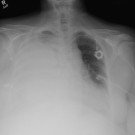

Preslav Valchev, MD; Jerry Kenmoe, MD; Narjis Batool, MD

A 74-year-old woman with a past medical history of stage 4 invasive ductal carcinoma presented to the emergency department with fatigue and gradually worsening dyspnea during the past 2 months.